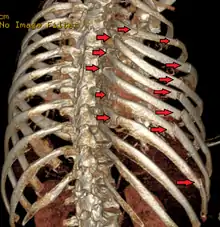

| A 3D reconstruction from a CT scan showing a flail chest. Arrows mark the rib fractures. | |